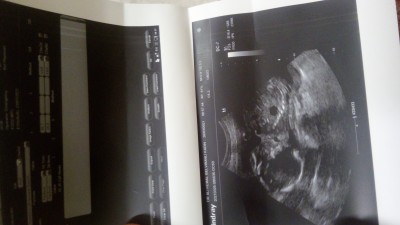

Kızlar devlet hastanesıne geldım.Bu kagıtta boy kılo yazmıyormu?Yazmıyorsa nıye kendılerı soylemıyorlar acaba?Kagıtta yazıyordur dıye sormadan cıktım ben odadan sinir oldum.

Gebelik haftası 22+2

Her hafta boy kilo ayrintisi vermez. Kagitlarinizda hafta detaylari verilen trrimler var. Resimlerini goremedigim icin birsey diyemiyorum ama. Efw kilosunu FL x7 boyunu veriyor.

Canım sağ köşede yazar ya boyu kilosu gün yazar

Efw yazacak o kilo ac boy

Küçük haftalarda pek söylenmiyor evelsi gün gittim kağıta gr mı yazıyordu boyuda fl ile 7 yi çarparak öğreniyoruz

FL 70.26 dıyor o muki?